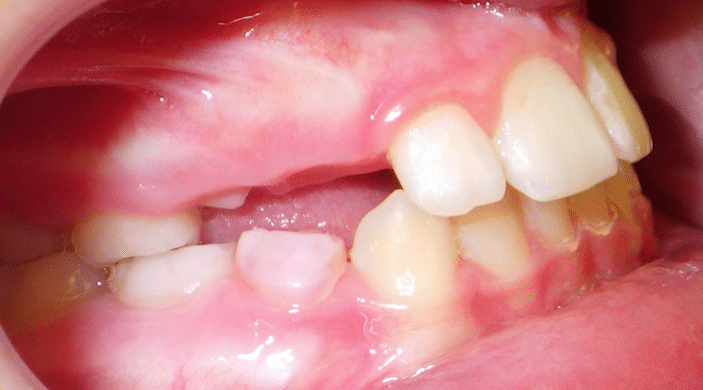

Our patient, Luke, presented with an underbite. We began Phase I with him in October 2018 and were able to achieve major changes in Luke’s profile and bite. Also note how his upper lip changed as well. Luke’s photos show how well growth modification can work in an adolescent patient, even preventing the need for jaw surgery as an adult.